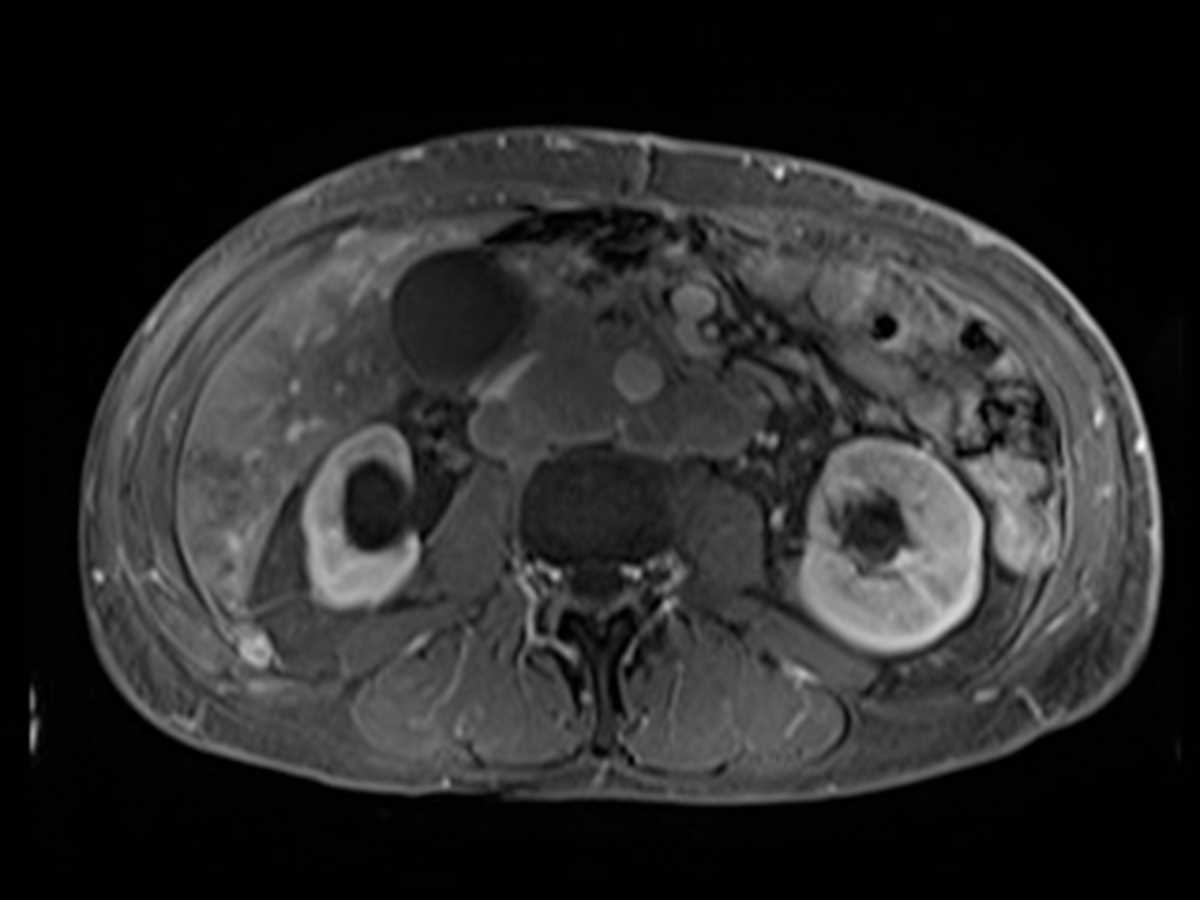

Intraductal Papillary Mucinous Neoplasm (IPMN) Body of Pancreas